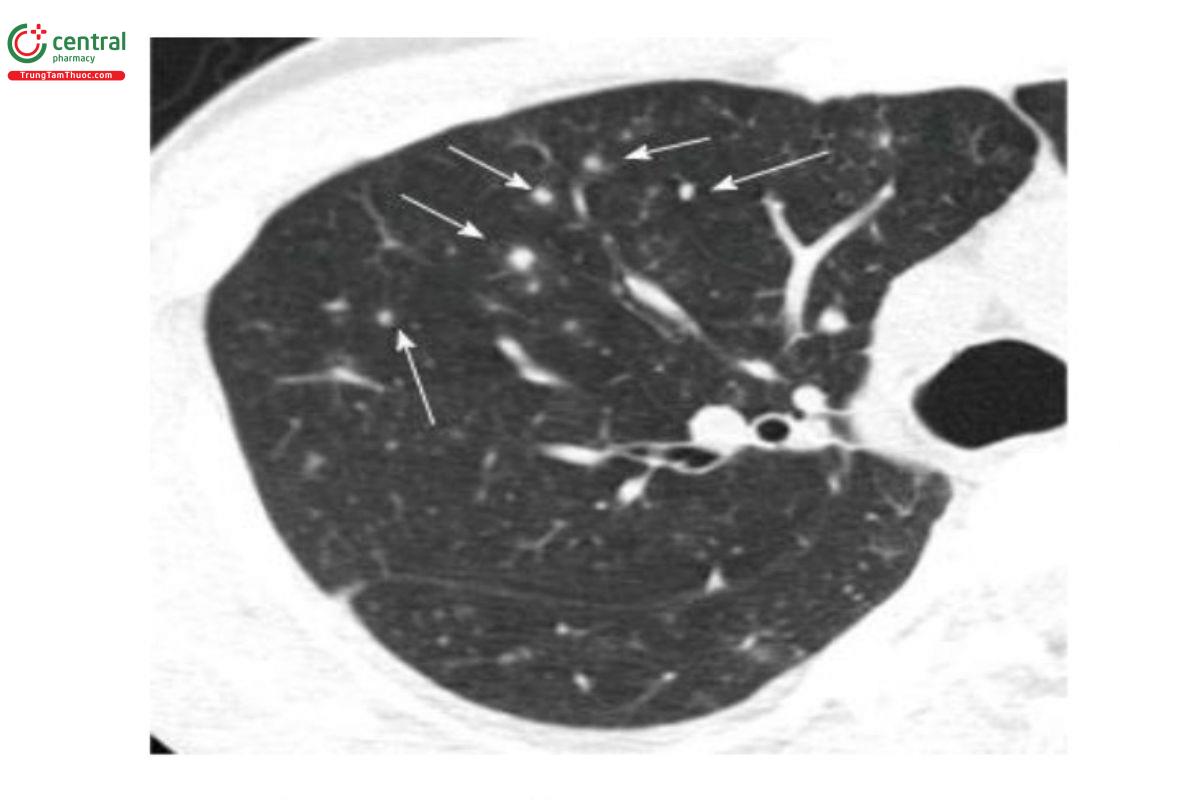

Tổn thương các nốt phân bố ngẫu nhiên chiếm ưu thế: Các nốt phân bố ngẫu nhiên có thể được tạo ra do sự lây truyền vi sinh qua đường máu (lao kê, nghẽn mạch nhiễm trùng) hoặc u hạt nhiễm trùng (lao, NTM, nấm). Một số viêm phổi do virus như Varicella-Zoster có tổn thương đặc trưng là các nốt phân bố ngẫu nhiên [1, 4].

Chú thích: Các nốt mờ nhỏ, thuần nhất, rải rác không liên quan đến các cấu trúc trung tâm tiểu thùy (Mũi tên).